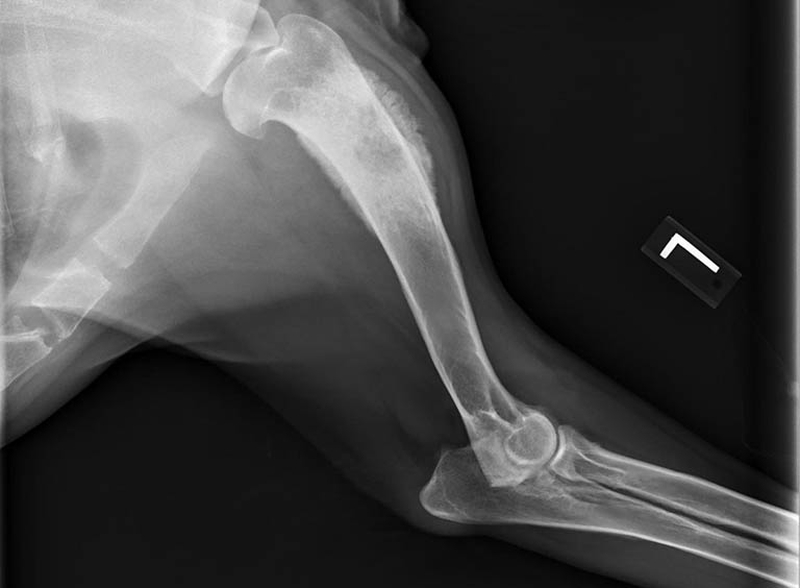

Chụp X-quang là phương pháp phản ánh hình ảnh của các cấu trúc bên trong cơ thể bằng cách sử dụng một lượng nhỏ bức xạ. Các bác sĩ sẽ chụp X-quang ở những khu vực bị sưng phù hoặc có u cục. Đây rất có thể là dấu hiệu bất thường cảnh báo sự xuất hiện của Sarcoma xương.

Chụp X-quang cho kết quả chính xác về Sarcoma xương